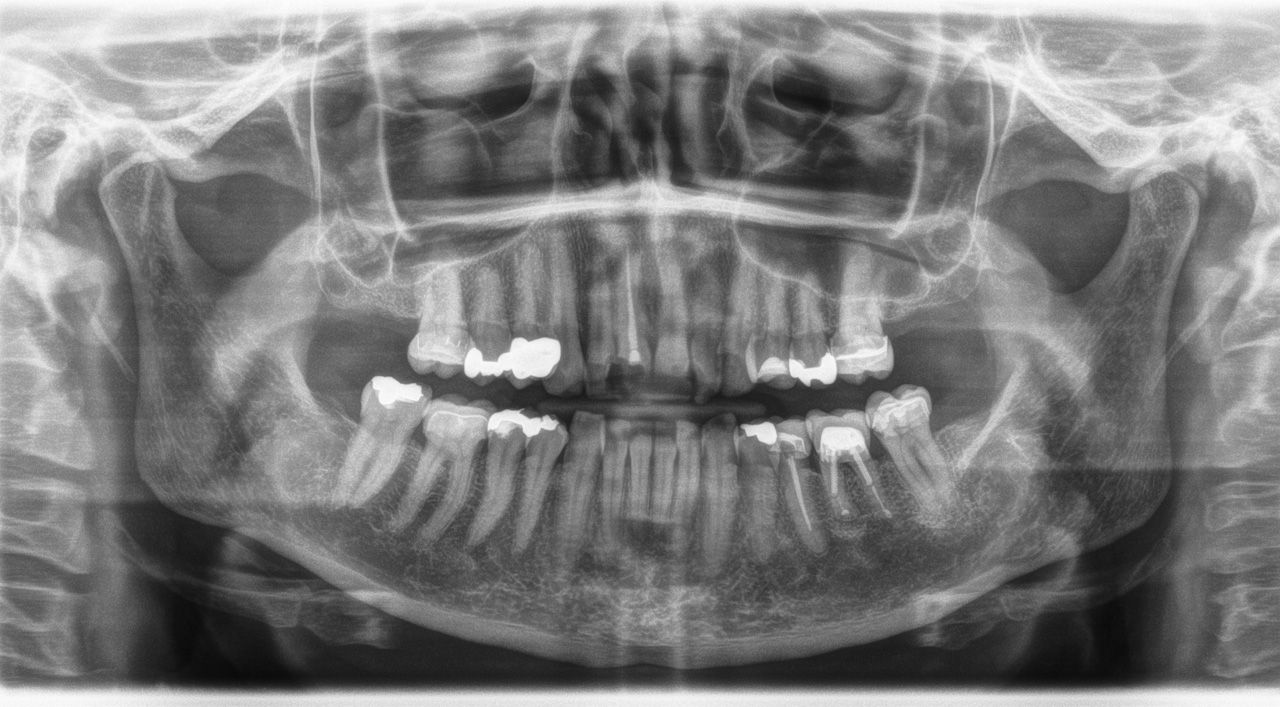

Dentition badly damaged by periodontitis